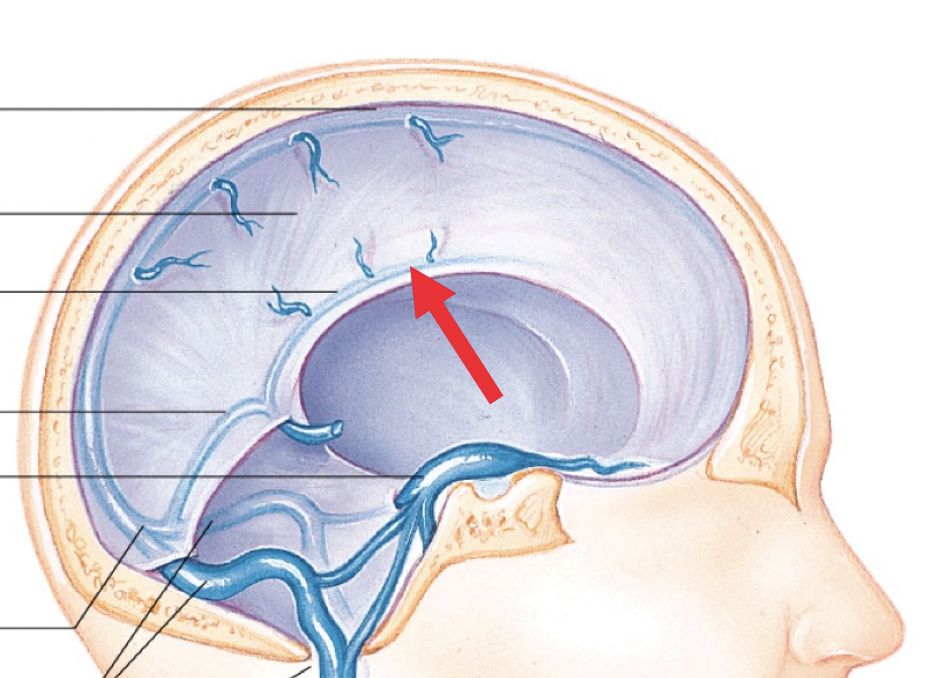

Arachnoid granulations

Drain CSF into venous sinuses

What is the subarachnoid space?

Where are the 4 main cisterns in the skull?

Where are the apertures and communication systems of the ventricular system?

Where is CSF generated?

Choroid plexus in inferior horn and body

What are the 8 steps/stages of CSF flow around the skull?